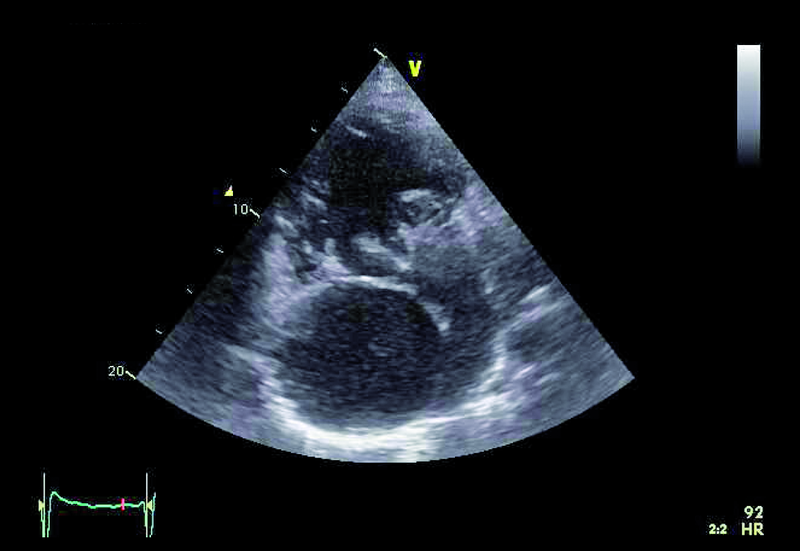

Mężczyzna, lat 31, z wrodzoną wadą serca o typie serca jednokomorowego, zastawkowego i podzastawkowego zwężenia tętnicy płucnej przeszedł w siódmym roku życia zabieg korekcji wady metodą Fontana-Linsa w ośrodku za granicą. Chory od kilku lat gorzej tolerował wysiłek. Rozpoznano napadowe, a następnie utrwalone migotanie przedsionków. Zdarzały się także obrzęki kończyn dolnych, powiększenie obwodu brzucha. Chory negował występowanie sinicy. W badaniu fizykalnym stwierdzono u niego szmer holosystoliczny nad sercem (3/6 w skali Levina), płyn w jamie opłucnej oraz wodobrzusze. Zwrócono uwagę, że w ostatnich latach saturacja spoczynkowa zmniejszyła się z 97 do 90%, a maksymalne zużycie tlenu w teście ergospirometrycznym wyniosło 13,8 ml/kg/min, co stanowiło 31% wartości należnej dla płci i wieku. Stwierdzono silnie wyrażone cechy zespołu enteropatii z hipoproteinemią. W chwili hospitalizacji leczony był dwoma środkami moczopędnymi, beta-adrenolitykiem oraz inhibitorem ACE. Otrzymywał także leczenie przeciwkrzepliwe. Wobec złego stanu ogólnego pacjenta wykonano cewnikowanie serca, stwierdzając ciśnienie w prawym przedsionku 13 mm Hg, średnie ciśnienie w tętnicach płucnych 14 mm Hg, opór płucny 0,2 j.W. Prawy przedsionek był w badaniach istotnie powiększony. Stwierdzano także poszerzenie żyły głównej dolnej (do 36 mm) z cechami samoistnego kontrastowania.

Operację Fontana, będącą rodzajem zabiegu paliatywnego, wykonuje się w celu korekcji zaburzeń hemodynamicznych towarzyszących wspólnej komorze. Celem operacji jest zmniejszenie przeciążenia objętościowego komory, ponieważ otrzymuje ona napływ zarówno z żył płucnych, jak i systemowych. Jest wiele rodzajów serca jednokomorowego. Najczęściej spotyka się zespół z atrezją trójdzielną, niedorozwojem lewej komory, zarośnięciem tętnicy płucnej, dwunapływową komorą lewą, dwuodpływową komorą lewą lub prawą. W podanym przykładzie można wyróżnić dwie zastawki przedsionkowo-komorowe, a więc krew wpływa do wspólnej komory (anatomicznie lewej) zarówno przez ujście trójdzielne, jak i mitralne, co dowodzi obecności komory dwunapływowej (ryc. 1-4). Celem operacji w tym wypadku było nie tylko oddzielenie spływu z żył systemowych, ale także zwiększenie całkowitej objętości krwi płynącej przez łożysko tętnic płucnych. Jak oceniać echokardiograficznie pacjenta po operacji metodą Fontana? Nie dziwi, że wspólna komora jest powiększona (ryc. 1, 2, 5), przerośnięta (ryc. 1, 2) i wykazuje upośledzoną kurczliwość. Jeśli wykształcone są dwie zastawki przedsionkowo-komorowe, należy ocenić każdą z nich, ponieważ fale zwrotne powodowane przez zastawki mogą zwiększać objętość komory i niekorzystnie wpływać na funkcję kurczliwą mięśnia. Niedomykalność zastawek przedsionkowo-komorowych (w podanym przykładzie umiarkowana [ryc. 5]) może także zwiększać ciśnienie w jamie lewego przedsionka, co zmniejsza konieczny dla wytworzonego zespolenia gradient ciśnień: żyła systemowa – tętnica płucna – lewy przedsionek. Wynikiem zmniejszania się gradientu może być narastanie ciśnienia w kanale Fontana (ryc. 1-3), pojawienie się hepatomegalii, przesięków do jam ciała, zespołu enteropatii z hipoproteinemią. Niemal u wszystkich chorych po operacji Fontana obserwuje się poszerzenie światła żyły głównej dolnej ze zwolnieniem przepływu krwi i zjawiskiem samokontrastowania się. Nie zawsze udaje się precyzyjnie uwidocznić morfologię wykonanego zespolenia. W tym wypadku mieliśmy do czynienia z tzw. starym jego rodzajem, polegającym na bezpośrednim połączeniu prawego przedsionka z pniem tętnicy płucnej bezpośrednio (ryc. 6). Metoda taka (Fontana-Linsa) stosowana była w latach 70. i 80. ubiegłego stulecia. W przypadku ciężkiego upośledzenia funkcji kurczliwej wspólnej komory, braku zwężenia w kanale Fontana i wykluczenia istotnych niedomykalności zastawek przedsionkowo-komorowych postępowaniem z wyboru pozostaje zabieg przeszczepienia serca, do którego chory został zakwalifikowany.